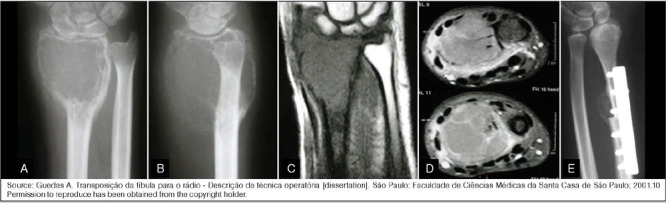

Abstract Image